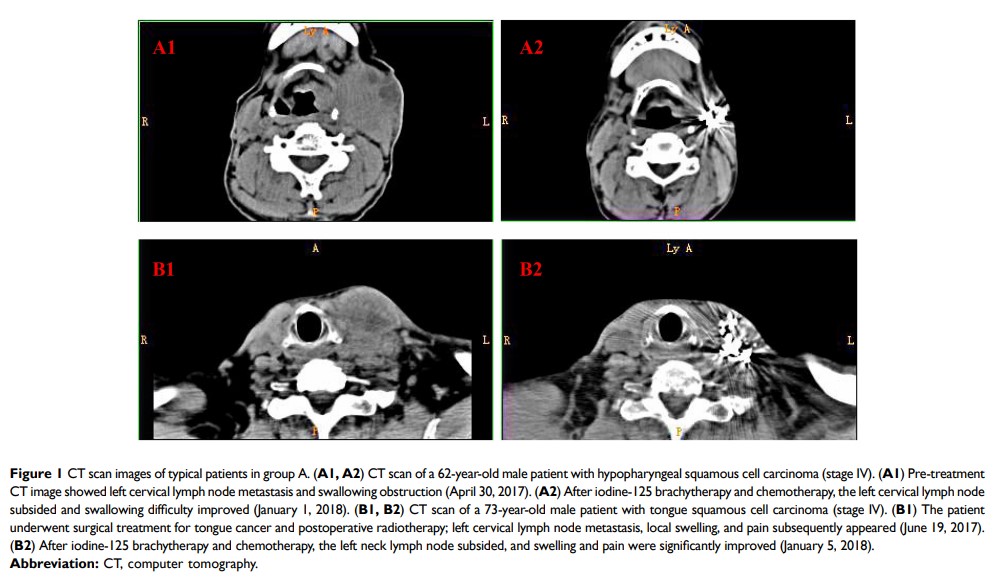

碘 125 近距离放射疗法治疗复发性或转移性头颈部鳞状细胞癌的疗效和安全性